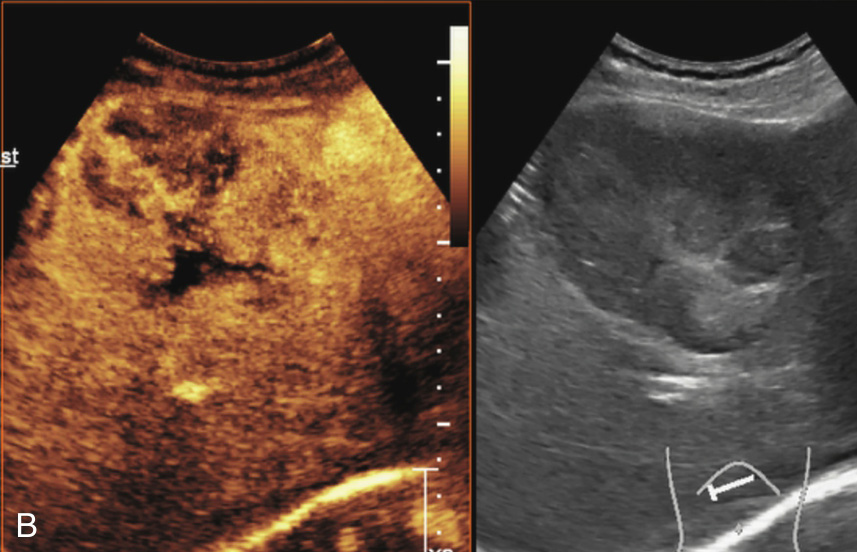

图1-7-4 肝内胆管细胞癌灰阶超声图像

肝右叶见较大混合回声,形态不规则,边界欠清